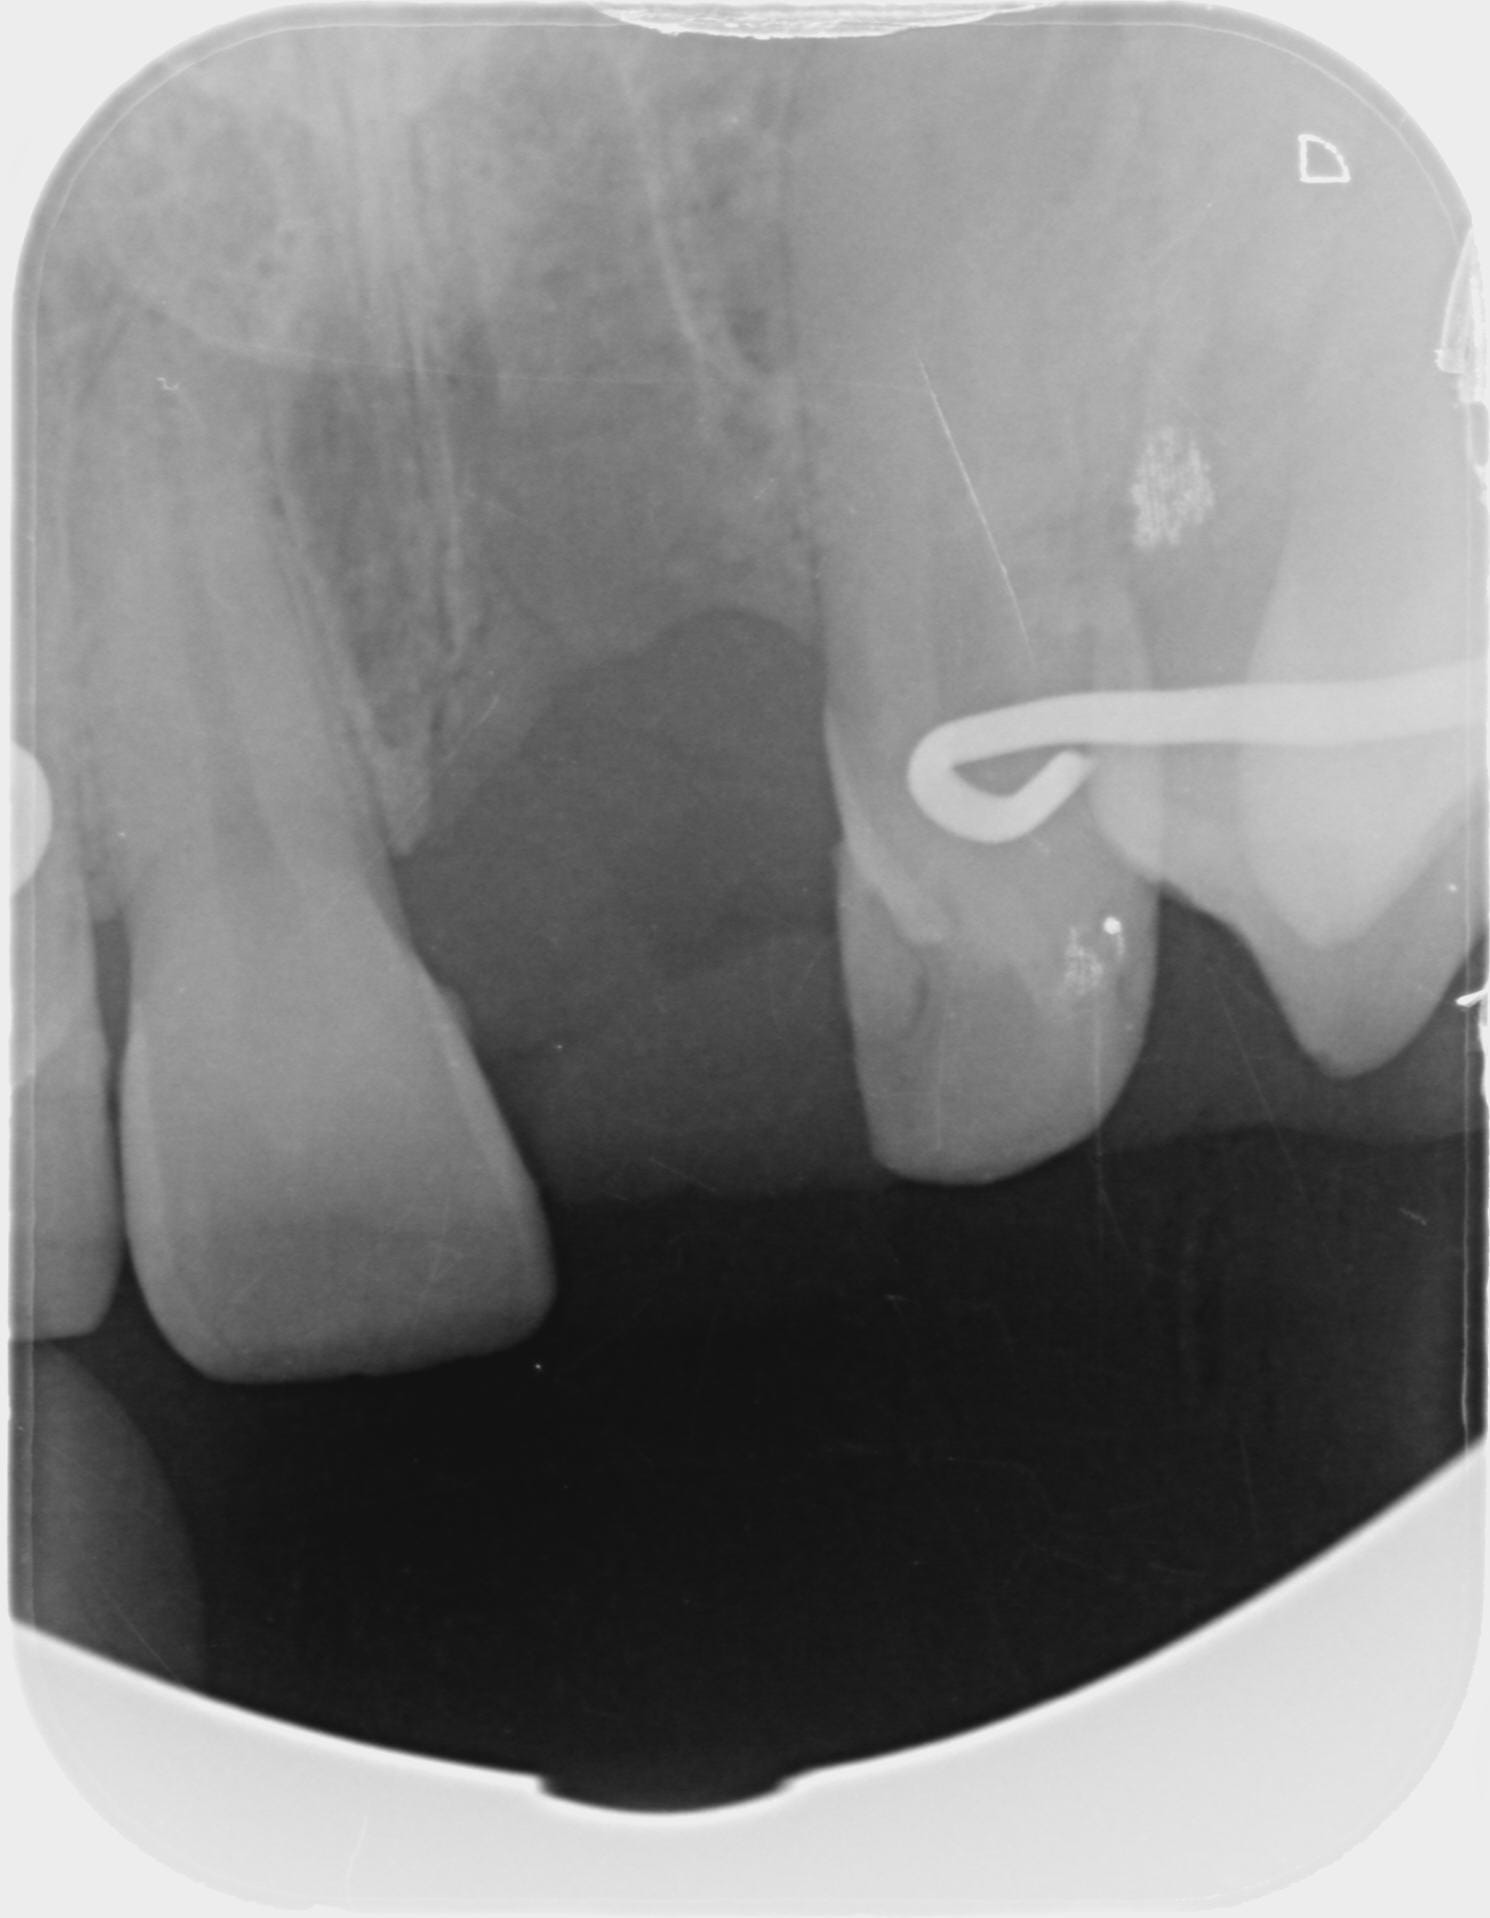

Voici pour la panoramique à 6 jours post op.

Les sinus paraissent clairs.

Pano uiihvz - Eugenol

Euh... ton implant est très très enfoui esthétiquement je pense que ça va pas être une super surprise (même si elle recouvre, pense que les patients regardent toujours en soulevant la lèvre...) ensuite par rapport à l'apex de ta 11 il semble très haut, je ferai une 3D perso pour voir mon plancher des fosses nasales.